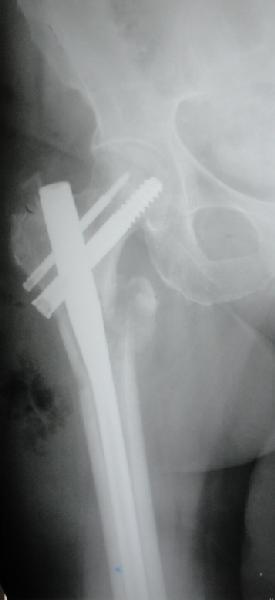

До выхода блокируемых гвоздей для фиксации косых подвертельных переломов в основном применяли Blade Plate. За счет уникальной конструкции создавался Fixed Angled Device, который соединял головку с диафизом, минуя зону перелома.

За счет особой конструкции клинка и подпорки (buttress) в диафиз создавалась стабильность, и предупреждалось скольжение по линии перелома. Перпендикулярная поверхность клинка предупреждала сгибательные и разгибательные смещения, и в сравнении с круглым винтом редко происходило прорезыванием.

Первые реконструкционные гвозди без блокировки винтов не смогли повторить преимущества, и из-за Z эффекта винтов происходило быстрое расшатывание.

С приходом менее агрессивных блокируемых цефаломедуллярных гвоздей (Gamma 3 и другие) изменилась тактика лечения. Несмотря на то, что вся стабильность держится вокруг одного блокирующего винта, в большинстве случаев гвозди приводили к успеху.

В данном случае в головке бедра и в вертлужной впадине огромный дефект, навряд ли удалением импланта или заменой на другой можно сохранить сустав.

Вашему вниманию представляется похожий случай, пациентке 70, осложнился в течение одного месяца после операции. Ревизия с заменой сустава, кабельная фиксация на трохантер. При установке в дистальном диафизе обнаружен тонкий кортикальный слой и сделана профилактика от возможного перелома аллографтом.